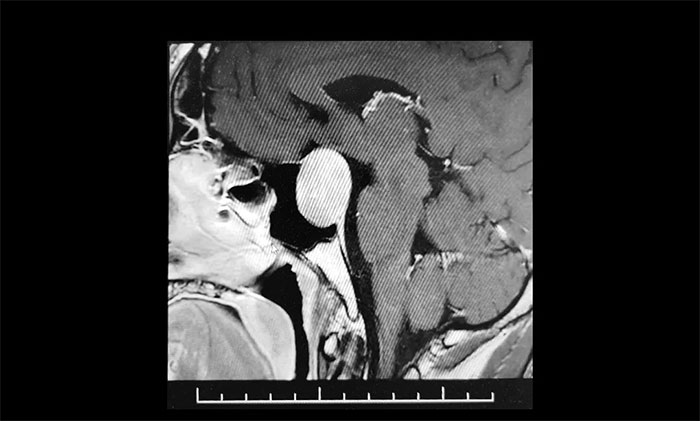

今年38歲的張先生,是江蘇人。去年9月份開始,自感左眼視力下降、視物不清,在當(dāng)?shù)蒯t(yī)院眼科檢查,左眼視力測(cè)不出,外側(cè)視野缺損,查不出病因。今年2月中旬,在另一家醫(yī)院檢查,經(jīng)頭顱MRI檢測(cè),發(fā)現(xiàn)垂體巨大占位,考慮為垂體腺瘤。

▲ 腫瘤侵襲生長(zhǎng),包繞左側(cè)海綿竇

為求進(jìn)一步確定病情,張先生在家人陪伴下,慕名來(lái)到上海藍(lán)十字腦科醫(yī)院。經(jīng)鞍區(qū)MRI平掃+增強(qiáng)顯示:蝶鞍顯著擴(kuò)大,鞍底下陷,垂體窩見(jiàn)類橢圓形異常信號(hào),大小約3.1×2.7×2.1cm,病變向鞍上生長(zhǎng),推移視交叉上抬,與左側(cè)海綿竇分界欠清晰,被包裹1/2。

神經(jīng)外科6B病區(qū)專家李士其教授、潘仁龍主任、吳治群博士會(huì)診后,考慮為侵襲性垂體巨腺瘤,乒乓球大小的瘤體壓迫視神經(jīng),并且侵襲生長(zhǎng),左側(cè)海綿竇部分受包繞,向上已突破鞍隔,壓迫視神經(jīng)、視交叉、下丘腦。如果腫瘤進(jìn)一步生長(zhǎng),可能加重視力下降、甚至失明。